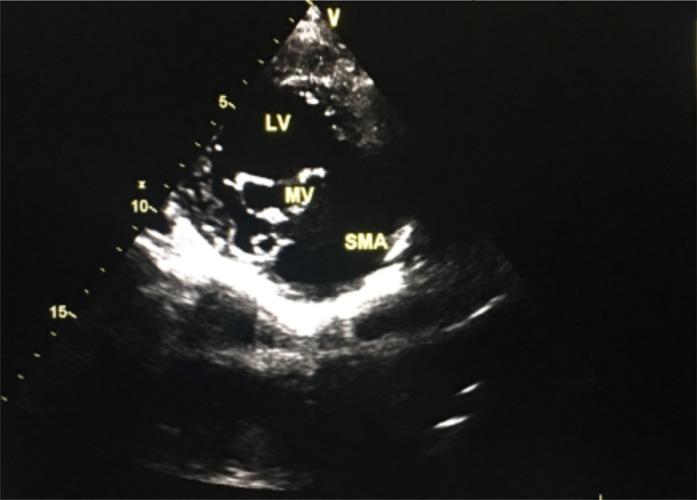

METHODS

In April 2017, a 25-year-old patient havingsubmitral left ventricular aneurysm with New York Heart Association (NYHA) class IV heart failure and mild left ventricular systolic dysfunctionreceived medical treatment at our institution. She had severe mitral regurgitation and aneurysmal thrombus. The diagnosis was easily made using GE Vivid E9 transthoracic echocardiography. She was given drugs for management of heart failure and anticoagulation.